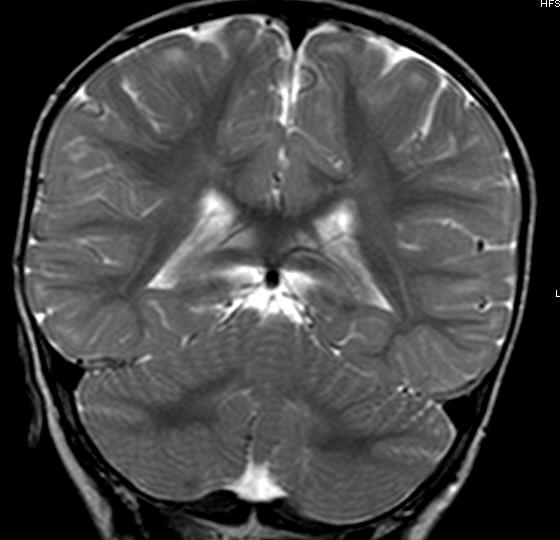

X-Linked Adrenoleukodystrophy X-Linked Adrenoleukodystrophy

• Confluent, symmetric deep WM w/ Confluent, symmetric deep WM w/ leading edge enhancement leading edge enhancement

• Posterior in 80% Posterior in 80%

• Pons and medulla Pons and medulla